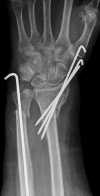

Diatal radius fractures (DRFs) are typical fractures of relatively fit persons with osteoporotic bone who remain active into older age. Traditionally, DRFs in older patients have been treated with closed reduction and cast immobilization. Considering the increasing life expectancy of the elderly population, appropriate management of these fractures is of growing importance. Decision making for surgical or nonsurgical approach to osteoporotic DRFs is difficult. These decisions are often made based on the data from treatments of much younger patients. The current literature concerning the treatment of DRFs in the elderly individuals is more controversial. Some investigators have recommended open reduction internal fixation (ORIF) as treatment for unstable DRFs in older patients, while others have suggested that elderly patients should be treated nonsurgically even if there is an unstable fracture situation because fracture reduction is not associated with functional outcomes as in younger patients. This article reviews the different treatment options for DRFs in the elderly individuals reported in the recent literature.